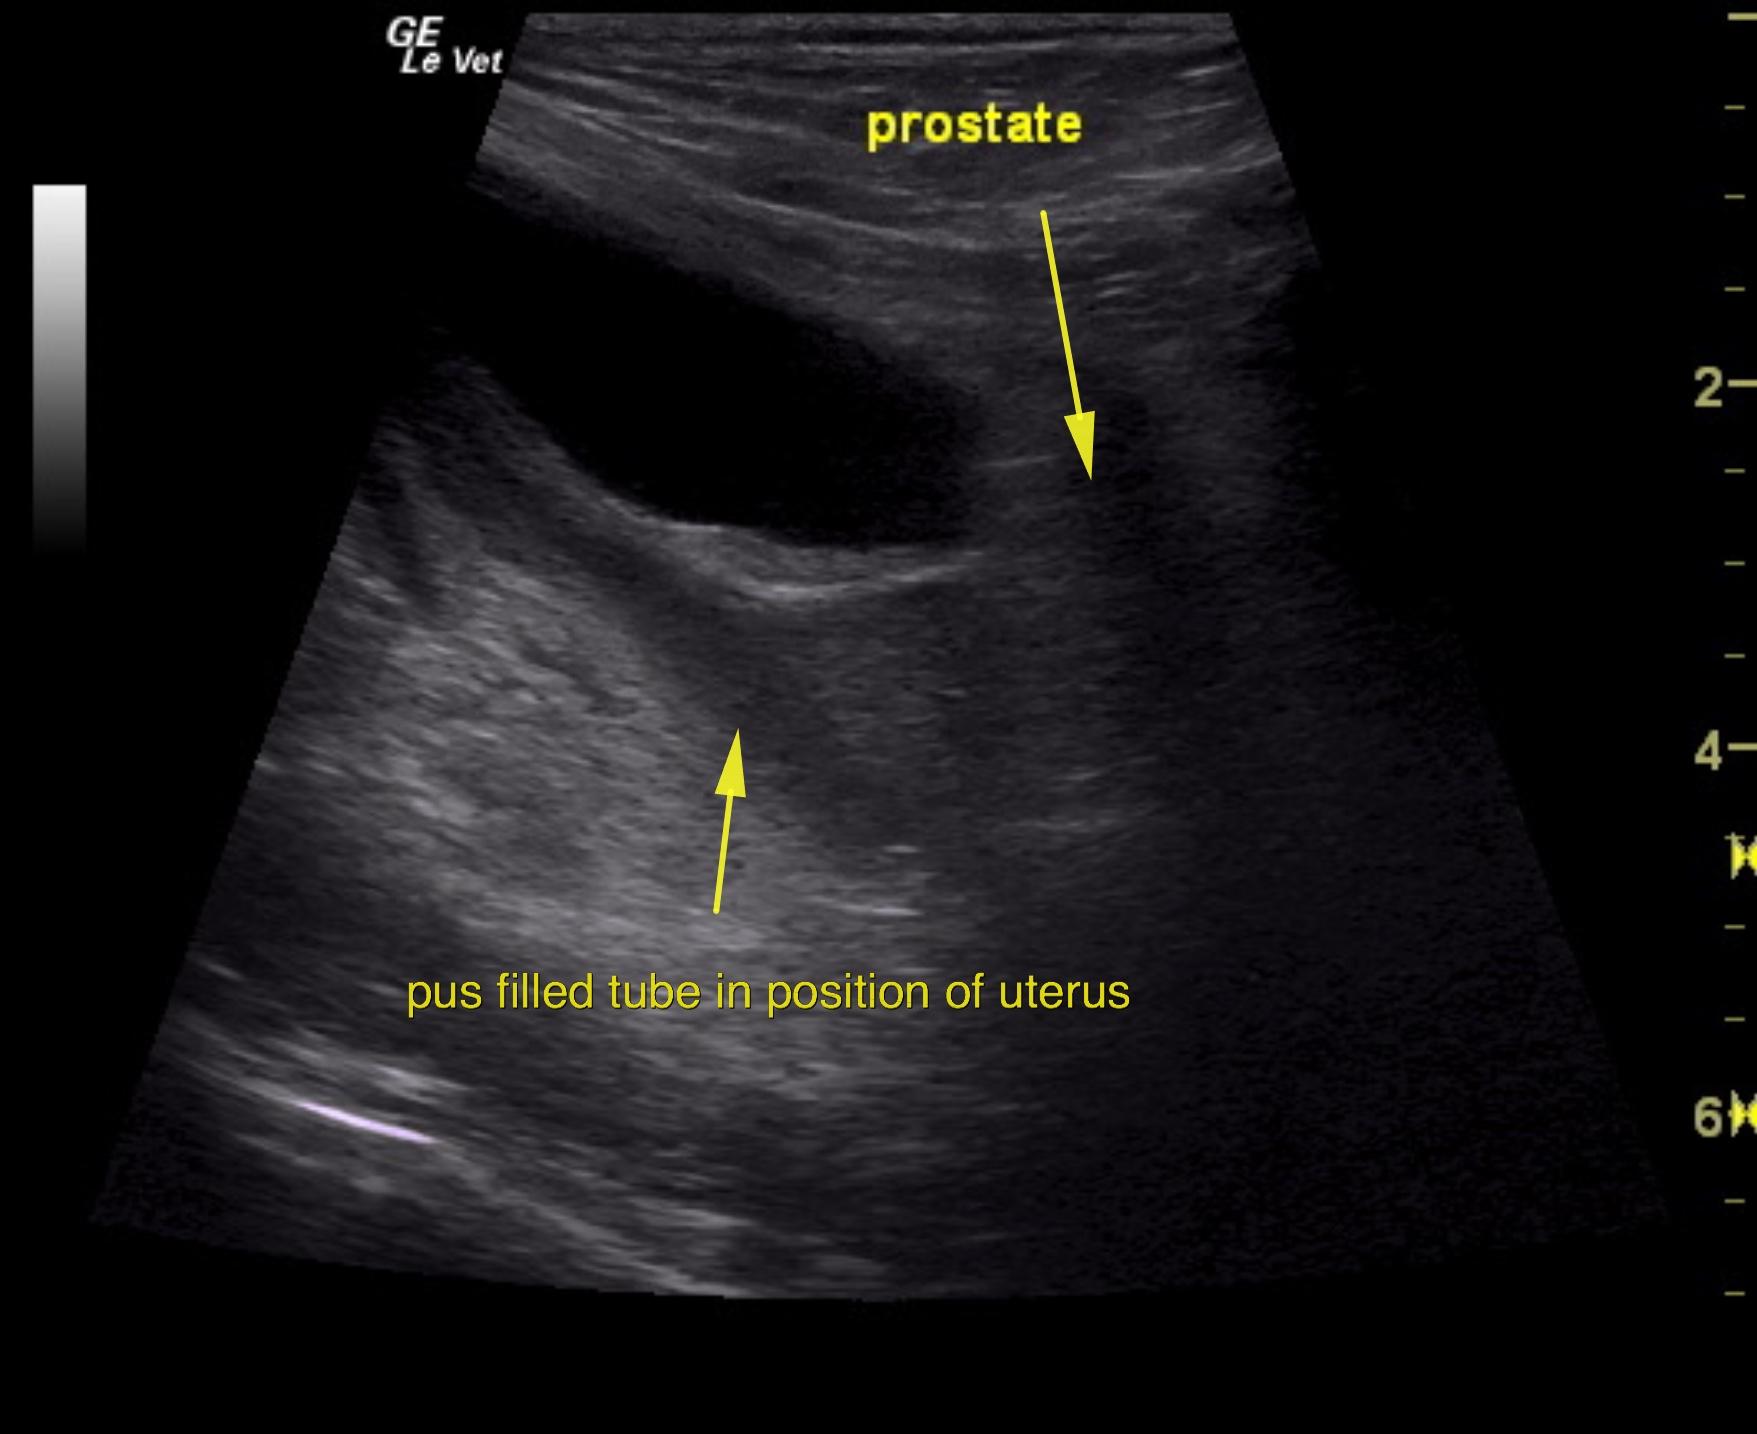

An 11-year-old NM Poodle was presented for evaluation of back pain and dark urine. Urinalysis and blood work were both unremarkable.

Purulent material was obtained on ultrasound-guided centesis without complications. However, reactive mesentery was noted throughout the pelvis. The position of this tube would fit with a uterus. This patient may be a hermaphrodite with secondary pyometra. I cannot make a direct connection from the tubular structure to the prostate itself as they appear to be separate. I recommend exploratory surgery with removal of this structure. The ureters do not appear to be involved. The position and structure would be that of a uterus. Therefore, treatment for pancreatitis and localized infection in the region of the pelvis would be recommended with IV fluid support, broad spectrum antibiotics such as Enrofloxacin and Clindamycin combination as well as exploratory surgery. If the tubular structure is confirmed to be a uterus and hermaphroditism then examination for possible ovaries would also be warranted even though none were visible in the image set. Regardless, this tubular structure necessitates surgical resection.

The urinary bladder itself presented minor thickening and minor debris. A tubular structure was noted in a position between the colon and the urinary bladder with dilation.

Pyometra in neutered male hermaphrodite

Exploratory surgery confirmed pyometra in a neutered male.